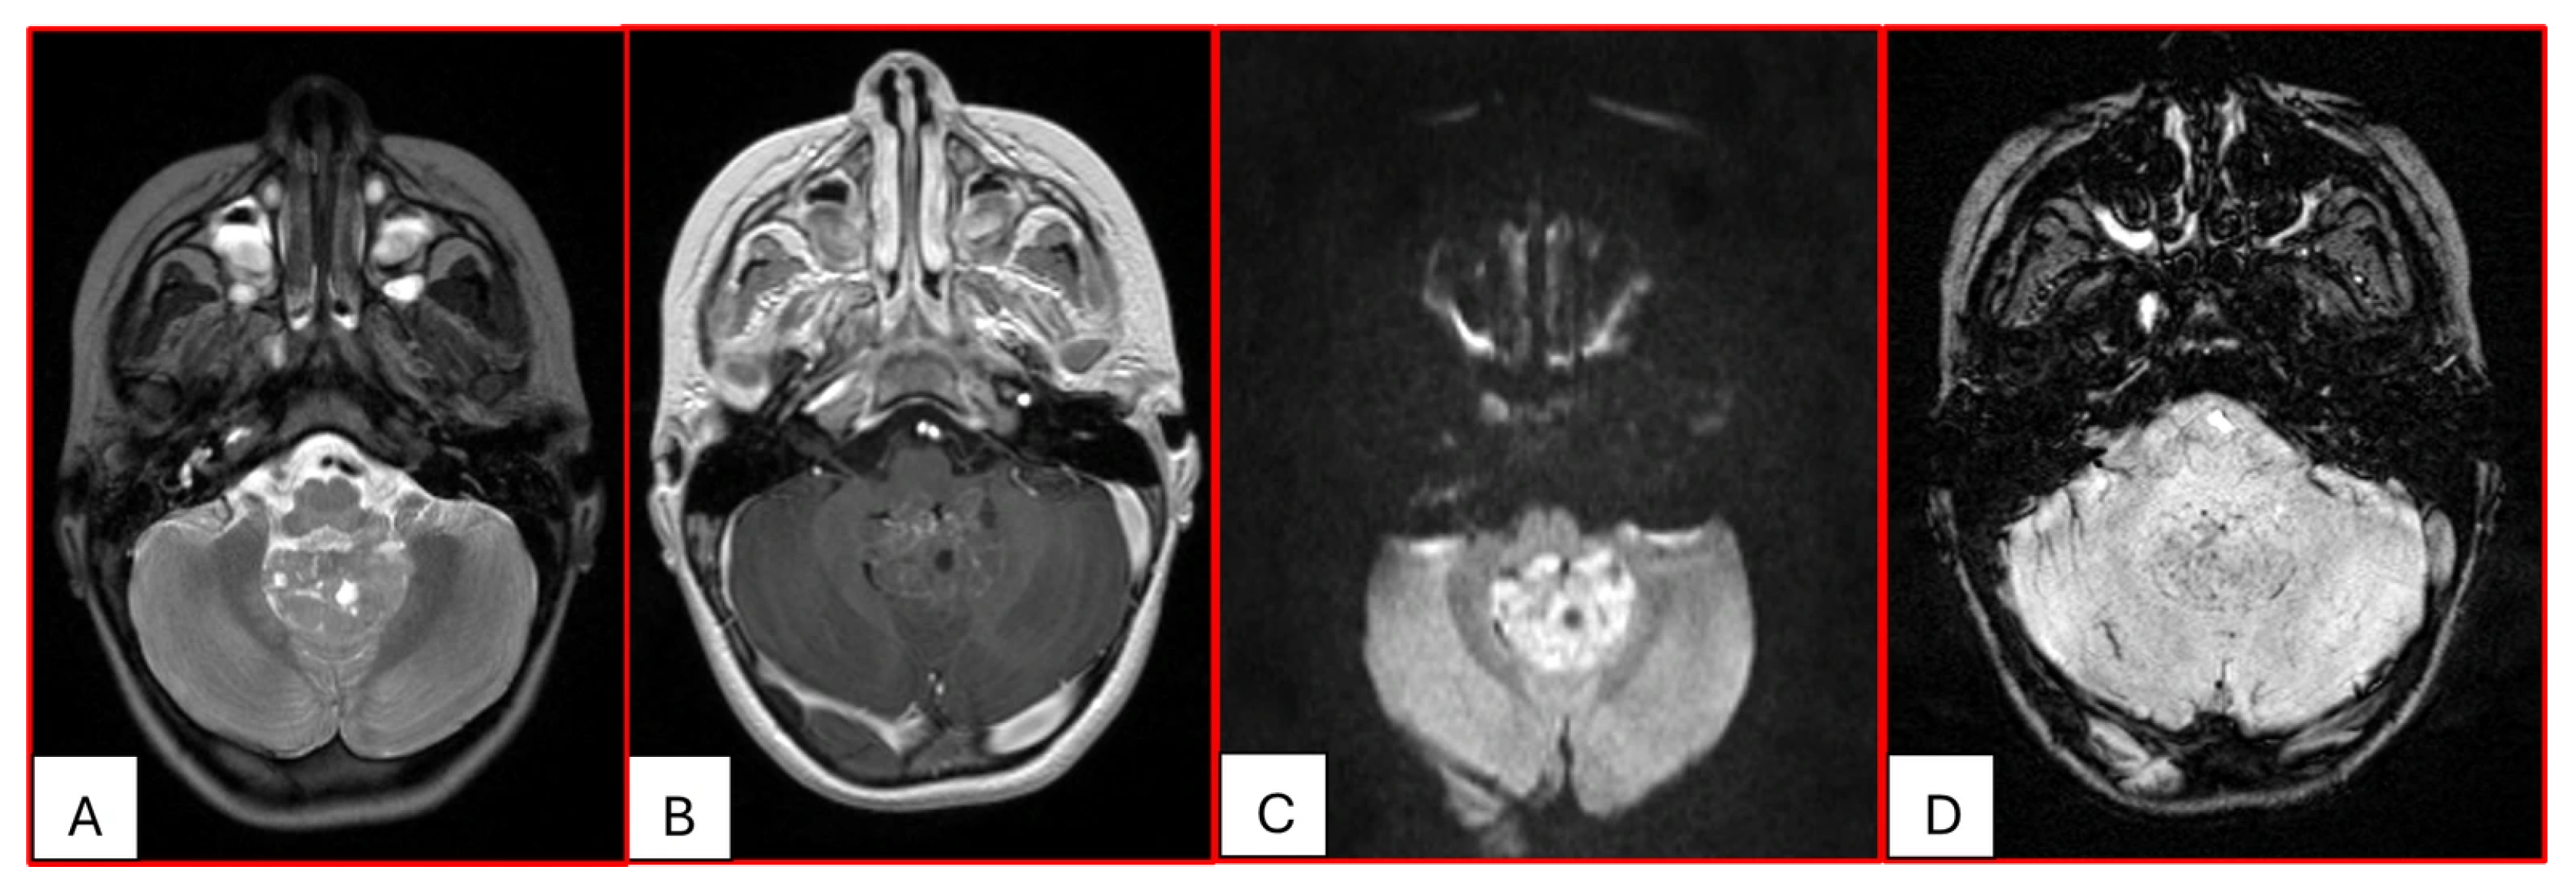

On computed tomography (CT), AT/RTs typically appear hyperdense owing to their high cellularity, and calcifications are frequently identified. Magnetic resonance imaging (MRI) findings are variable on both T1- and T2-weighted sequences; however, restricted diffusion is usually present. Cystic or necrotic components, as well as intratumoral hemorrhage, are common features [15]. Arslanoglu et al. described the presence of eccentrically positioned cysts with peripheral wall enhancement as a potentially distinguishing characteristic of infratentorial AT/RTs (Figure 1). The pattern and degree of contrast enhancement are variable, further reflecting the histopathologic heterogeneity of these neoplasms (Figure 2 and Figure 3). A characteristic pattern of band-like enhancement surrounding a central cystic or necrotic area was observed in 38% of MRIs from a series of 32 patients [16].

Imaging features of ATRT may overlap with those of other primitive neuroectodermal tumors, particularly Medulloblastoma in the posterior fossa (15), as the posterior fossa is the most common location for pediatric brain tumors. Utilizing advanced artificial intelligence (AI) algorithms to interpret medical imaging data may lead to tools for tumor segmentation; however, currently the imaging overlap of AT/RT, Medulloblastoma, and other CNS embryonal tumors that can occur in the posterior fossa does not allow for precise stratification within the posterior fossa embryonal tumor category [19].

Figure 3. Three-year-old female with ATRT. (A) Axial T2-weighted image shows a mass centered in the midline posterior fossa of heterogeneous intermediate signal with small cystic/necrotic changes. There is no surrounding edema. (B) This mass demonstrates mild heterogeneous enhancement. (C) There is prominent corresponding restricted diffusion. (D) A few foci of susceptibility are noted, which may reflect internal hemorrhage or calcifications. Note that the MRI features of this mass mimic the appearance of Medulloblastoma.